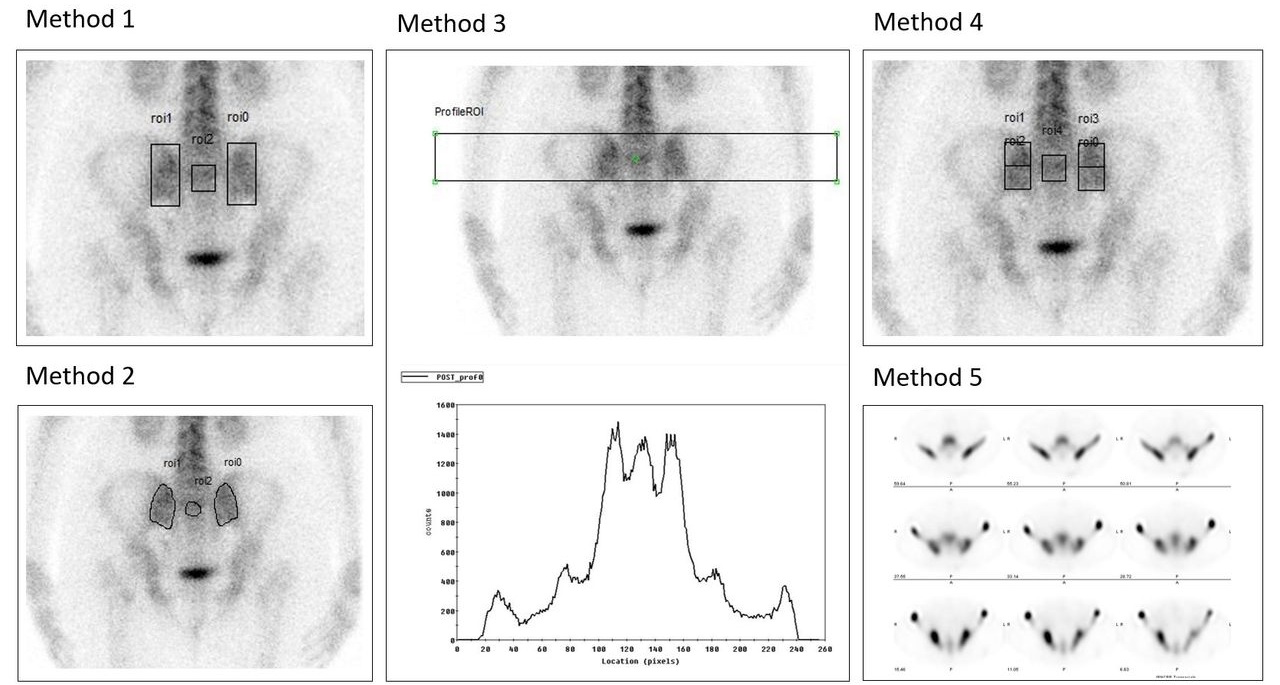

Sacroiliac Index (SII): rapporto tra l’attività delle articolazioni sacroiliache e quella del sacro. Valori superiori a 1.17-1.19 sono indicativi di sacroileite attiva.

Le immagini illustrano 6 approcci per valutare il SII.

Scintigrafia planare (metodi 1-4): calcolo del rapporto di captazione tramite ROI rettangolari globali (1), irregolari anatomiche (2), a profilo grafico orizzontale (3) o rettangolari suddivise in metà superiore/inferiore (4). SPECT (metodo 5): valutazione qualitativa (visual scoring) che confronta visivamente l’intensità delle articolazioni sacro-iliache rispetto al sacro (minore, uguale o maggiore). SPECT/TC (metodo 6 – immagini assiali): analisi quantitativa 3D tramite VOI. L’integrazione delle metodiche tomografiche (metodi 5 e 6) aggiunge valore e precisione quantitativa rispetto alle sole tecniche planari.